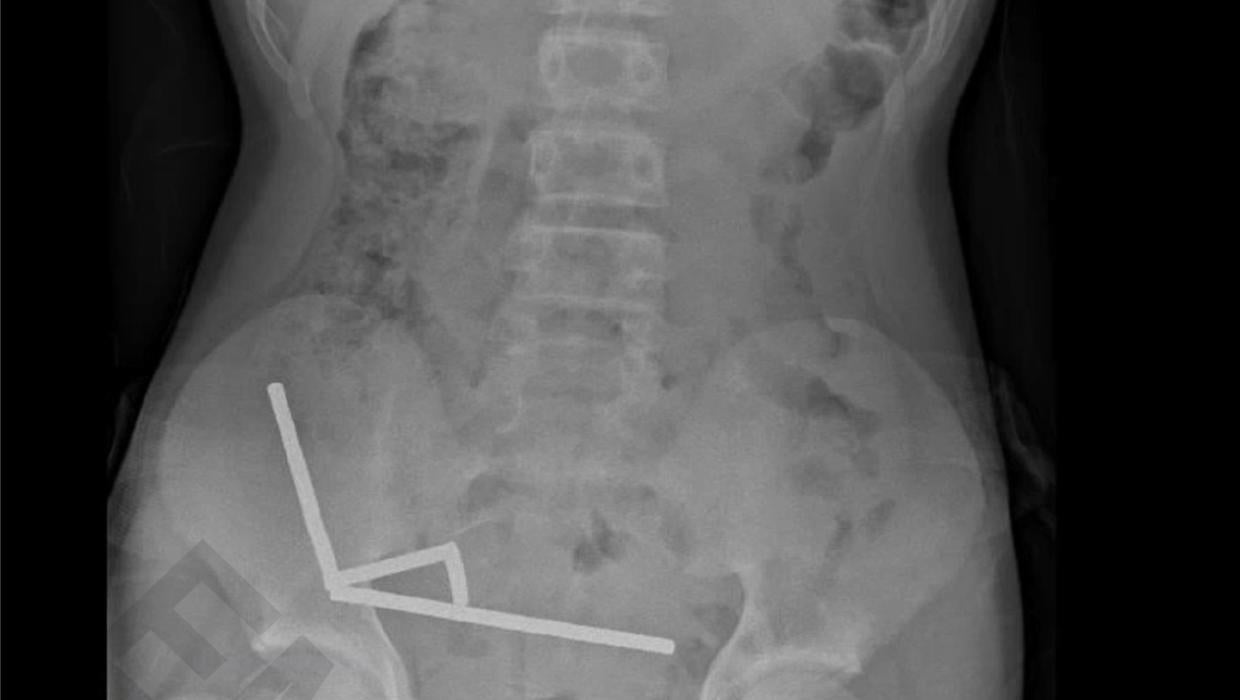

A 13-year-old boy faced a perilous health crisis after swallowing between 60 to 100 small magnets, necessitating emergency surgery at Tauranga Hospital in New Zealand. The incident, which occurred earlier this month, resulted in the removal of a portion of his bowel due to the severe internal damage caused by the magnets.

The boy was admitted to the hospital after experiencing significant abdominal pain, prompting immediate medical evaluation. Surgeons determined that the magnets had clumped together, leading to a blockage that could not be resolved through non-invasive measures.

The boy’s surgery, described as “major,” involved careful removal of the affected bowel section to restore normal function. Following the procedure, he remained under observation but is reported to be recovering well.